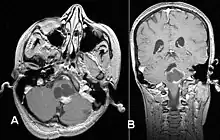

Pilocytic astrocytoma (and its variant pilomyxoid astrocytoma) is a brain tumor that occurs most commonly in children and young adults (in the first 20 years of life). They usually arise in the cerebellum, near the brainstem, in the hypothalamic region, or the optic chiasm, but they may occur in any area where astrocytes are present, including the cerebral hemispheres and the spinal cord. These tumors are usually slow growing and benign, corresponding to WHO malignancy grade 1.[1]

Usually – depending on the interview of the patient and after a clinical exam which includes a neurological exam and an ophthalmological exam – a CT scan and/or an MRI scan will be performed to confirm the presence of a tumor. They are usually easily distinguishable from normal brain structures using these imaging techniques. A special dye may be injected into a vein before these scans to provide contrast and make tumors easier to identify. Pilocytic astrocytomas are typically clearly visible on such scans, but it is often difficult to say based on imaging alone what type of tumor is present.